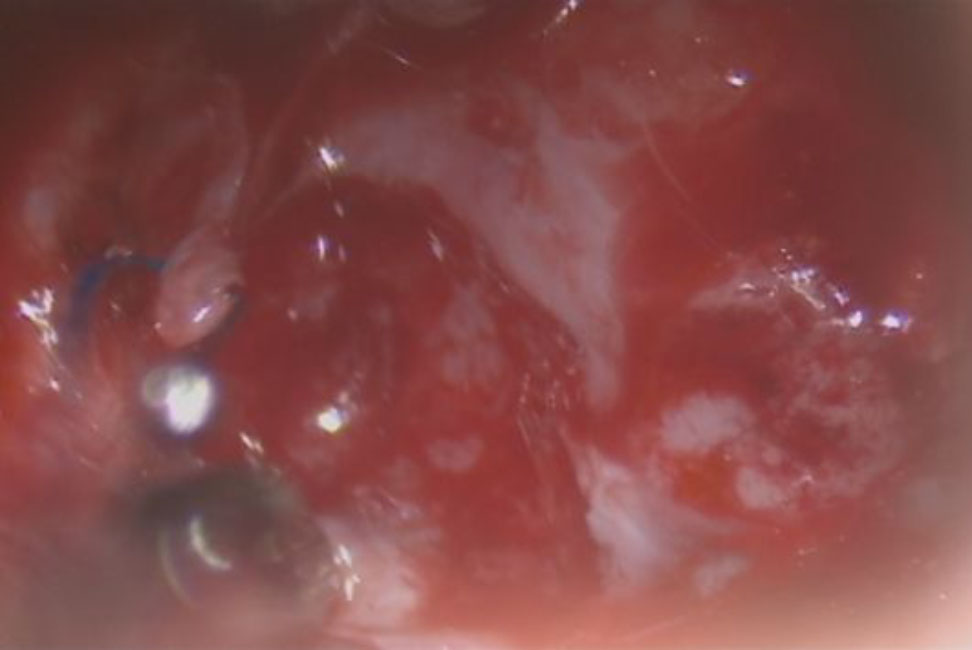

摘出 中

No.’25_108  摘出 中